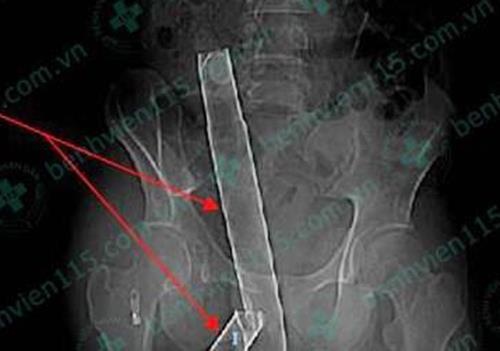

Bị ngã từ tầng trên của căn nhà, nạn nhân rơi trúng thanh inox phơi đồ dài 1,1 m dưới đất.

Ngày 12/6, thông tin từ Bệnh viện Đa khoa Trung ương Cần Thơ cho biết đơn vị này vừa cấp cứu thành công cho bệnh nhân Ro Ky Vah (21 tuổi, quốc tịch Campuchia).